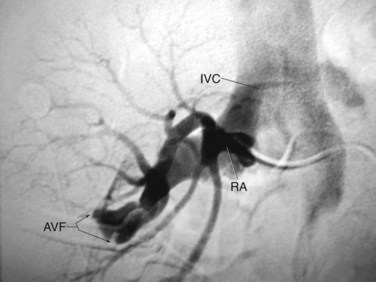

A ureteroscope passed retrograde can greatly facilitate percutaneous entry into the intrarenal collecting system (Grasso et al, 1995; Kidd and Conlin, 2003; Patel et al, 2008) by allowing the surgeon to observe and correct the percutaneous placement of a needle. A basket can then be passed through the ureteroscope to grasp the end of the percutaneous guidewire; pulling this out the urethra provides through-and-through access (Fig. 47–13). Even if the pathology being addressed is so large that direct visualization of the percutaneous needle is obscured (e.g., complete staghorn calculus), the ureteroscope can still be used to rapidly attain through-and-through access. Moreover, the ureteroscope may have better access to some sites in the kidney than the nephroscope and can be used to assist in the procedure (e.g., fragment or relocate stones, fulgurate small tumors).